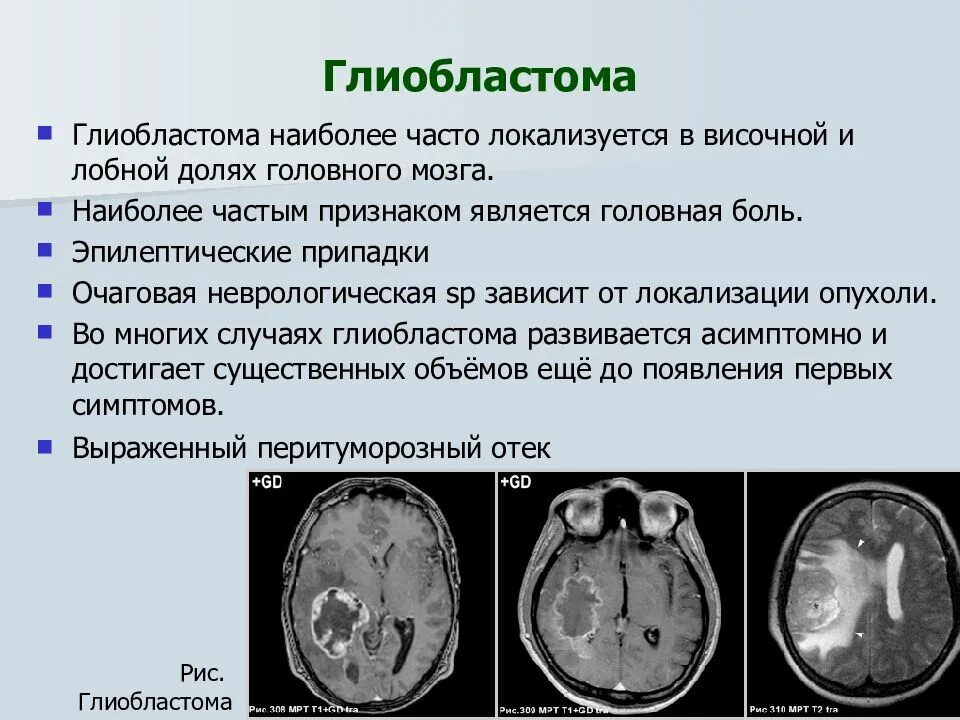

Компьютерная томография с болюсным контрастированием. Кт толстой кишки с контрастированием. Кт с болюсным контрастированием что это. Глиобластома мультиформная степень 4. Неоперабельная глиобластома головного мозга.. Глиобластома лобной доли мрт. Глиобластома злокачественная опухоль агрессивная.

Глиобластома мультиформная степень 4. Неоперабельная глиобластома головного мозга.. Глиобластома лобной доли мрт. Глиобластома злокачественная опухоль агрессивная. Филлоидная фиброаденома молочной железы УЗИ. УЗИ признаки доброкачественных опухолей молочных желез. Доброкачественная опухоль молочной железы на УЗИ. Опухоль молочной железы на УЗИ.